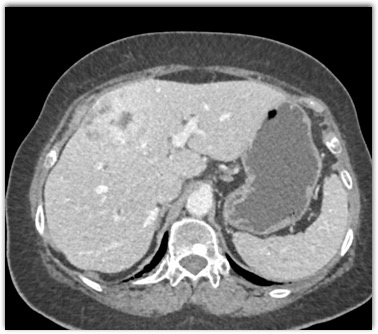

The most likely diagnosis in this case is

FNH

hepatic adenoma

hemangioma

hepatoma